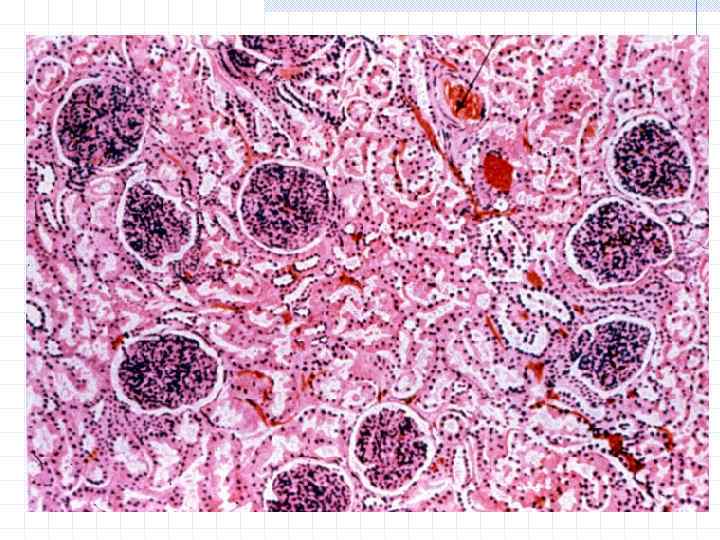

Симптомы подострого гломерулонефрита: фото и описание